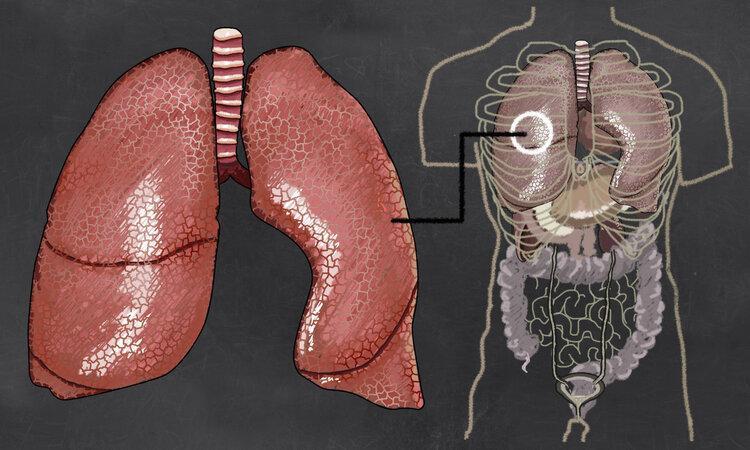

肺癌即原發性支氣管肺癌,是指發生在支氣管黏膜上皮的一種癌症。

肺癌常見的症狀一般有咳嗽(佔比8%—75%)、胸痛(佔比20%—49%)、胸悶氣急(佔比3%—60%)、痰中帶血(佔比6%—35%)、不明原因體重下降(0—68%)、聲音嘶啞(0—2%)等。